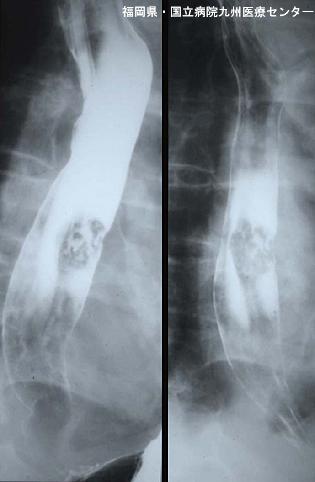

疾病(病理主体)的分类恶性上皮肿瘤/腺样囊肿癌

部位(按器官分)食道/中

检查方法X线

肿瘤的肉眼分类1型(肿瘤型)/

肿瘤最大直径30~34

肿瘤的深度sm